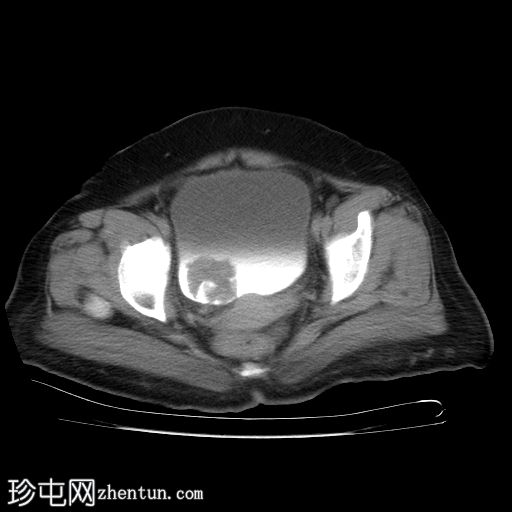

膀胱造影(静脉注射造影剂)

CT

轴位

平扫

膀胱内可见一边界清晰、不规则、可移动的软组织病变(CT值65 HU),直径约40 mm。病变无钙化,增强扫描后无强化。首要鉴别诊断为血肿。